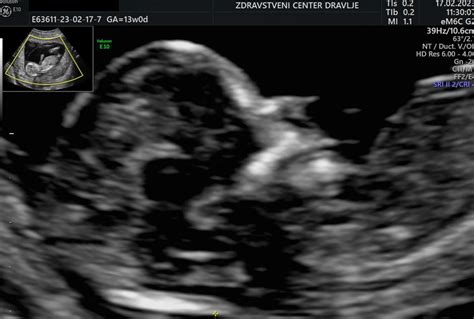

Do 10. tedna nosečnosti je razvojne nepravilnosti pri plodu težko ugotoviti. Te lahko začnejo ginekologi z večjo zanesljivostjo opazovati po 12. tednu, ko je na primer že viden nepravilen razvoj možganov. Lahko se opazi, da plod nima okončin ali da srce ni pravilno razvito. Pri nekaterih se razvojne nepravilnosti pokažejo že zelo zgodaj, pri drugih pozneje. Če ima plod povečano nuhalno svetlino, se opravijo kromosomske analize in že med 12. in 14. tednom lahko ugotovijo, da plod nima pravilne sestave kromosomov.

V Sloveniji se večina prekinitev nosečnosti zaradi razvojnih nepravilnosti izvede pred 20. tednom. Pomembno je, da nosečnica pride na pregled nuhalne svetline k zdravniku z licenco, ki zna plod natančno pregledati. Naslednji ultrazvok, imenovan morfologija, se izvede med 20. in 24. tednom, ko ponovno lahko najdemo razvojne nepravilnosti. Pri nekaterih nepravilnostih je potrebno spremljanje nosečnosti in porod v ustanovi, ki otroku ob rojstvu lahko pomaga. Druge nepravilnosti so tako hude, da ima lahko otrok hude zdravstvene težave vse življenje.

Za prekinitev nosečnosti ob ugotovljenih hudih razvojnih nepravilnostih se ženska ali oba starša odločita po posvetu z zdravniki različnih specialnosti. Nepravilnost najprej ugotovijo ginekologi, ki nato po potrebi vključijo še genetike, pediatre, kirurge, psihologe, opravijo dodatne preiskave, kot so genetske analize in slikanja z magnetno resonanco. Nosečnici ali paru čim natančneje pojasnijo prognozo, kar ni vedno lahko. Ginekologi vsaki ženski med 11. in 14. tednom nosečnosti priporočajo ultrazvočni pregled ploda z oceno nuhalne svetline in s krvnim dvojnim testom. Čeprav ta pregled ni obvezen, se zanj odločijo skoraj vse nosečnice. Z natančnim pregledom ploda lahko v tej višini nosečnosti ginekologi ocenijo tveganje za kromosomske spremembe in zgodaj odkrijejo nekatere razvojne nepravilnosti ploda.